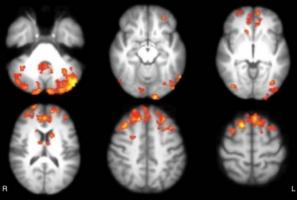

POLLUTION et DÉMENCE : Les particules fines font des corps de Lewy

Ce lien moléculaire entre les polluants atmosphériques et un risque accru de démence à corps de Lewy, identifié par une équipe de neuroscientifiques de la Columbia University's Mailman School of Public Health, met à nouveau en exergue les effets délétères des particules fines (PM2,5). Ces travaux, publiés dans la revue Science, s'ajoutent à un nombre croissant de preuves indiquant comment ces facteurs environnementaux déclenchent des modifications protéiques nocives dans le cerveau, responsables de neurodégénérescence.